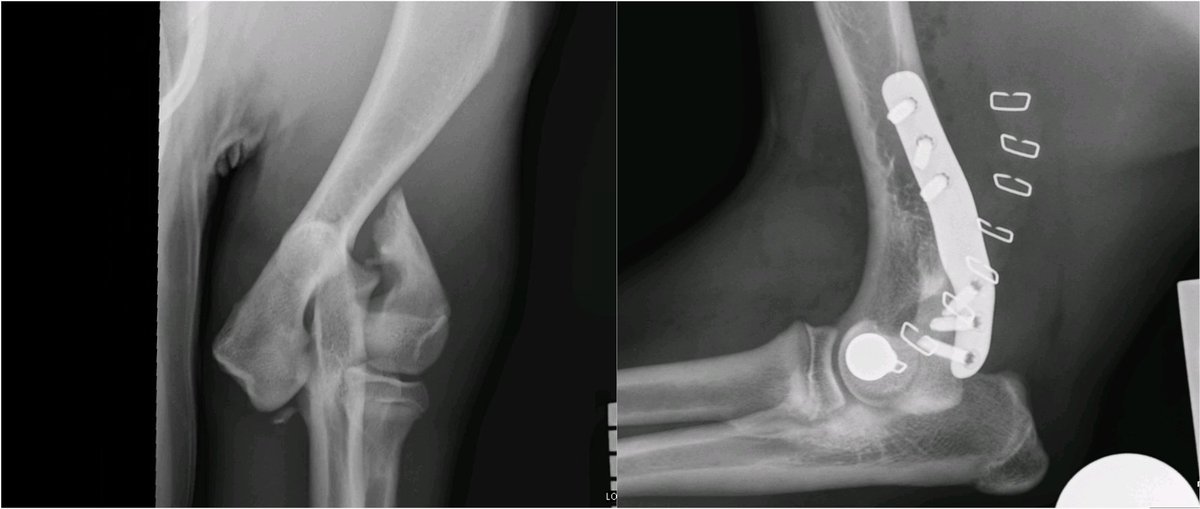

Did you know that baby Frenchies are particularly prone to elbow fractures?

Early and accurate repair is essential to restore and maintain a healthy elbow joint 💪🏻

We use custom 3D-printed implants designed specifically for French Bulldogs to optimise repair

Meet Mac and his unusual, spiral dicondylar fracture. Kept me and the fantastic @CGVetSpecialist team busy today. Thank heavens for the @FusionImplants LEAP to save a bit of time@near the end.

The Lateral Epicondylar Anatomical Plate from @FusionImplants is a great LEAP forwards. It makes repairing these fractures super-satisfying and provides a reliable locking plate construct for these dogs.